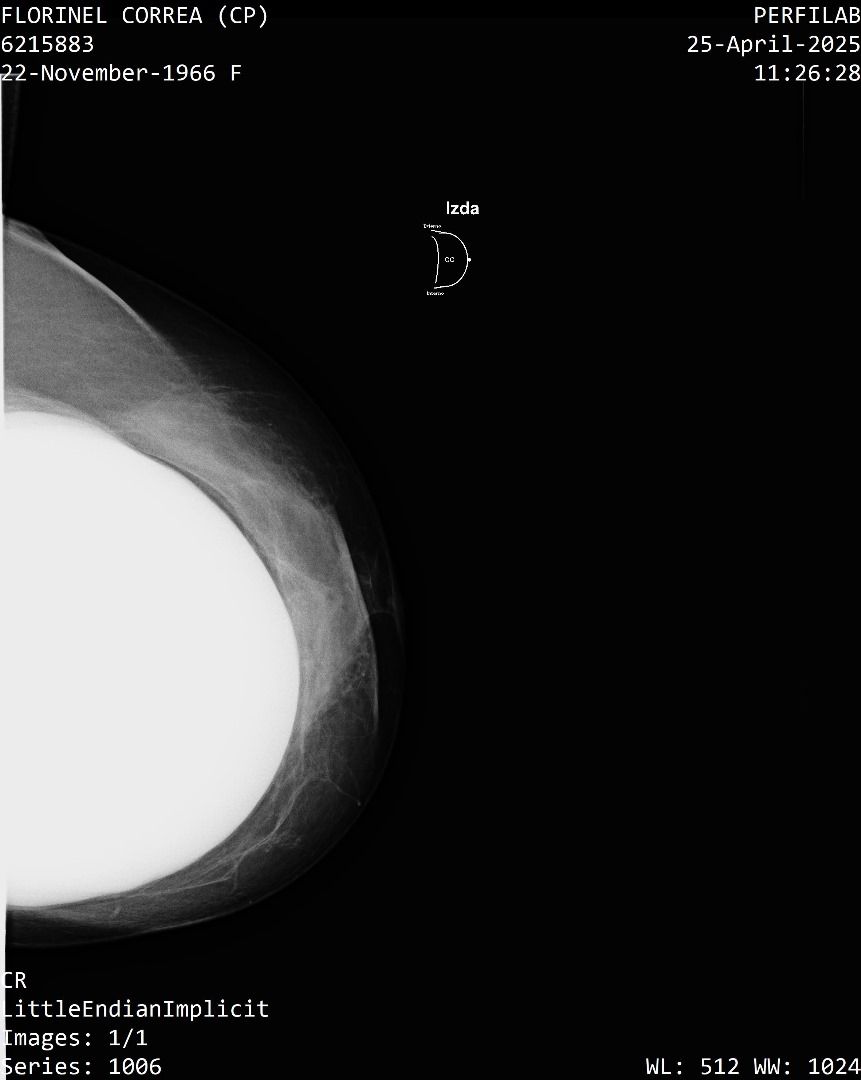

A Correa se le practicó un estudio de mamografía bilateral, la cual reporta una densidad mamaria heterogéneamente densa (ACR C), lo cual puede dificultar la detección de lesiones sospechosas.

Además, la presencia de implantes mamarios limita aún más la visibilidad del tejido mamario.

También se identificó un ganglio linfático de aspecto residual en la axila derecha que se considera sospechoso con este método, requiere evaluación urgente mediante ecografía mamaria.